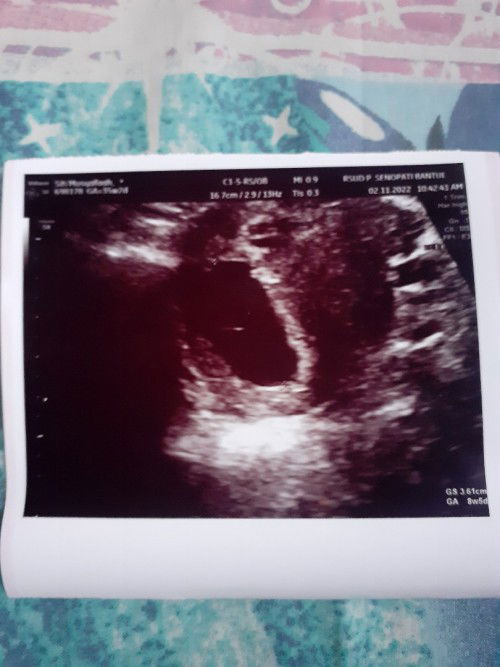

Td saya usg di uk 9w tapi cuma kelihatan kantung nya aja, apa bunda2 ada yg pernah ngalamin ?

coba cek di dokter yg lain bun, kok saya liatnya kaya ada janin ya, apa saya halu ya bun..

Usg abdomen atau trans V bun? Kl abdomen kayanya ada yg blm terlihat jg sih

dokter udah fix diagnosa BO bun?